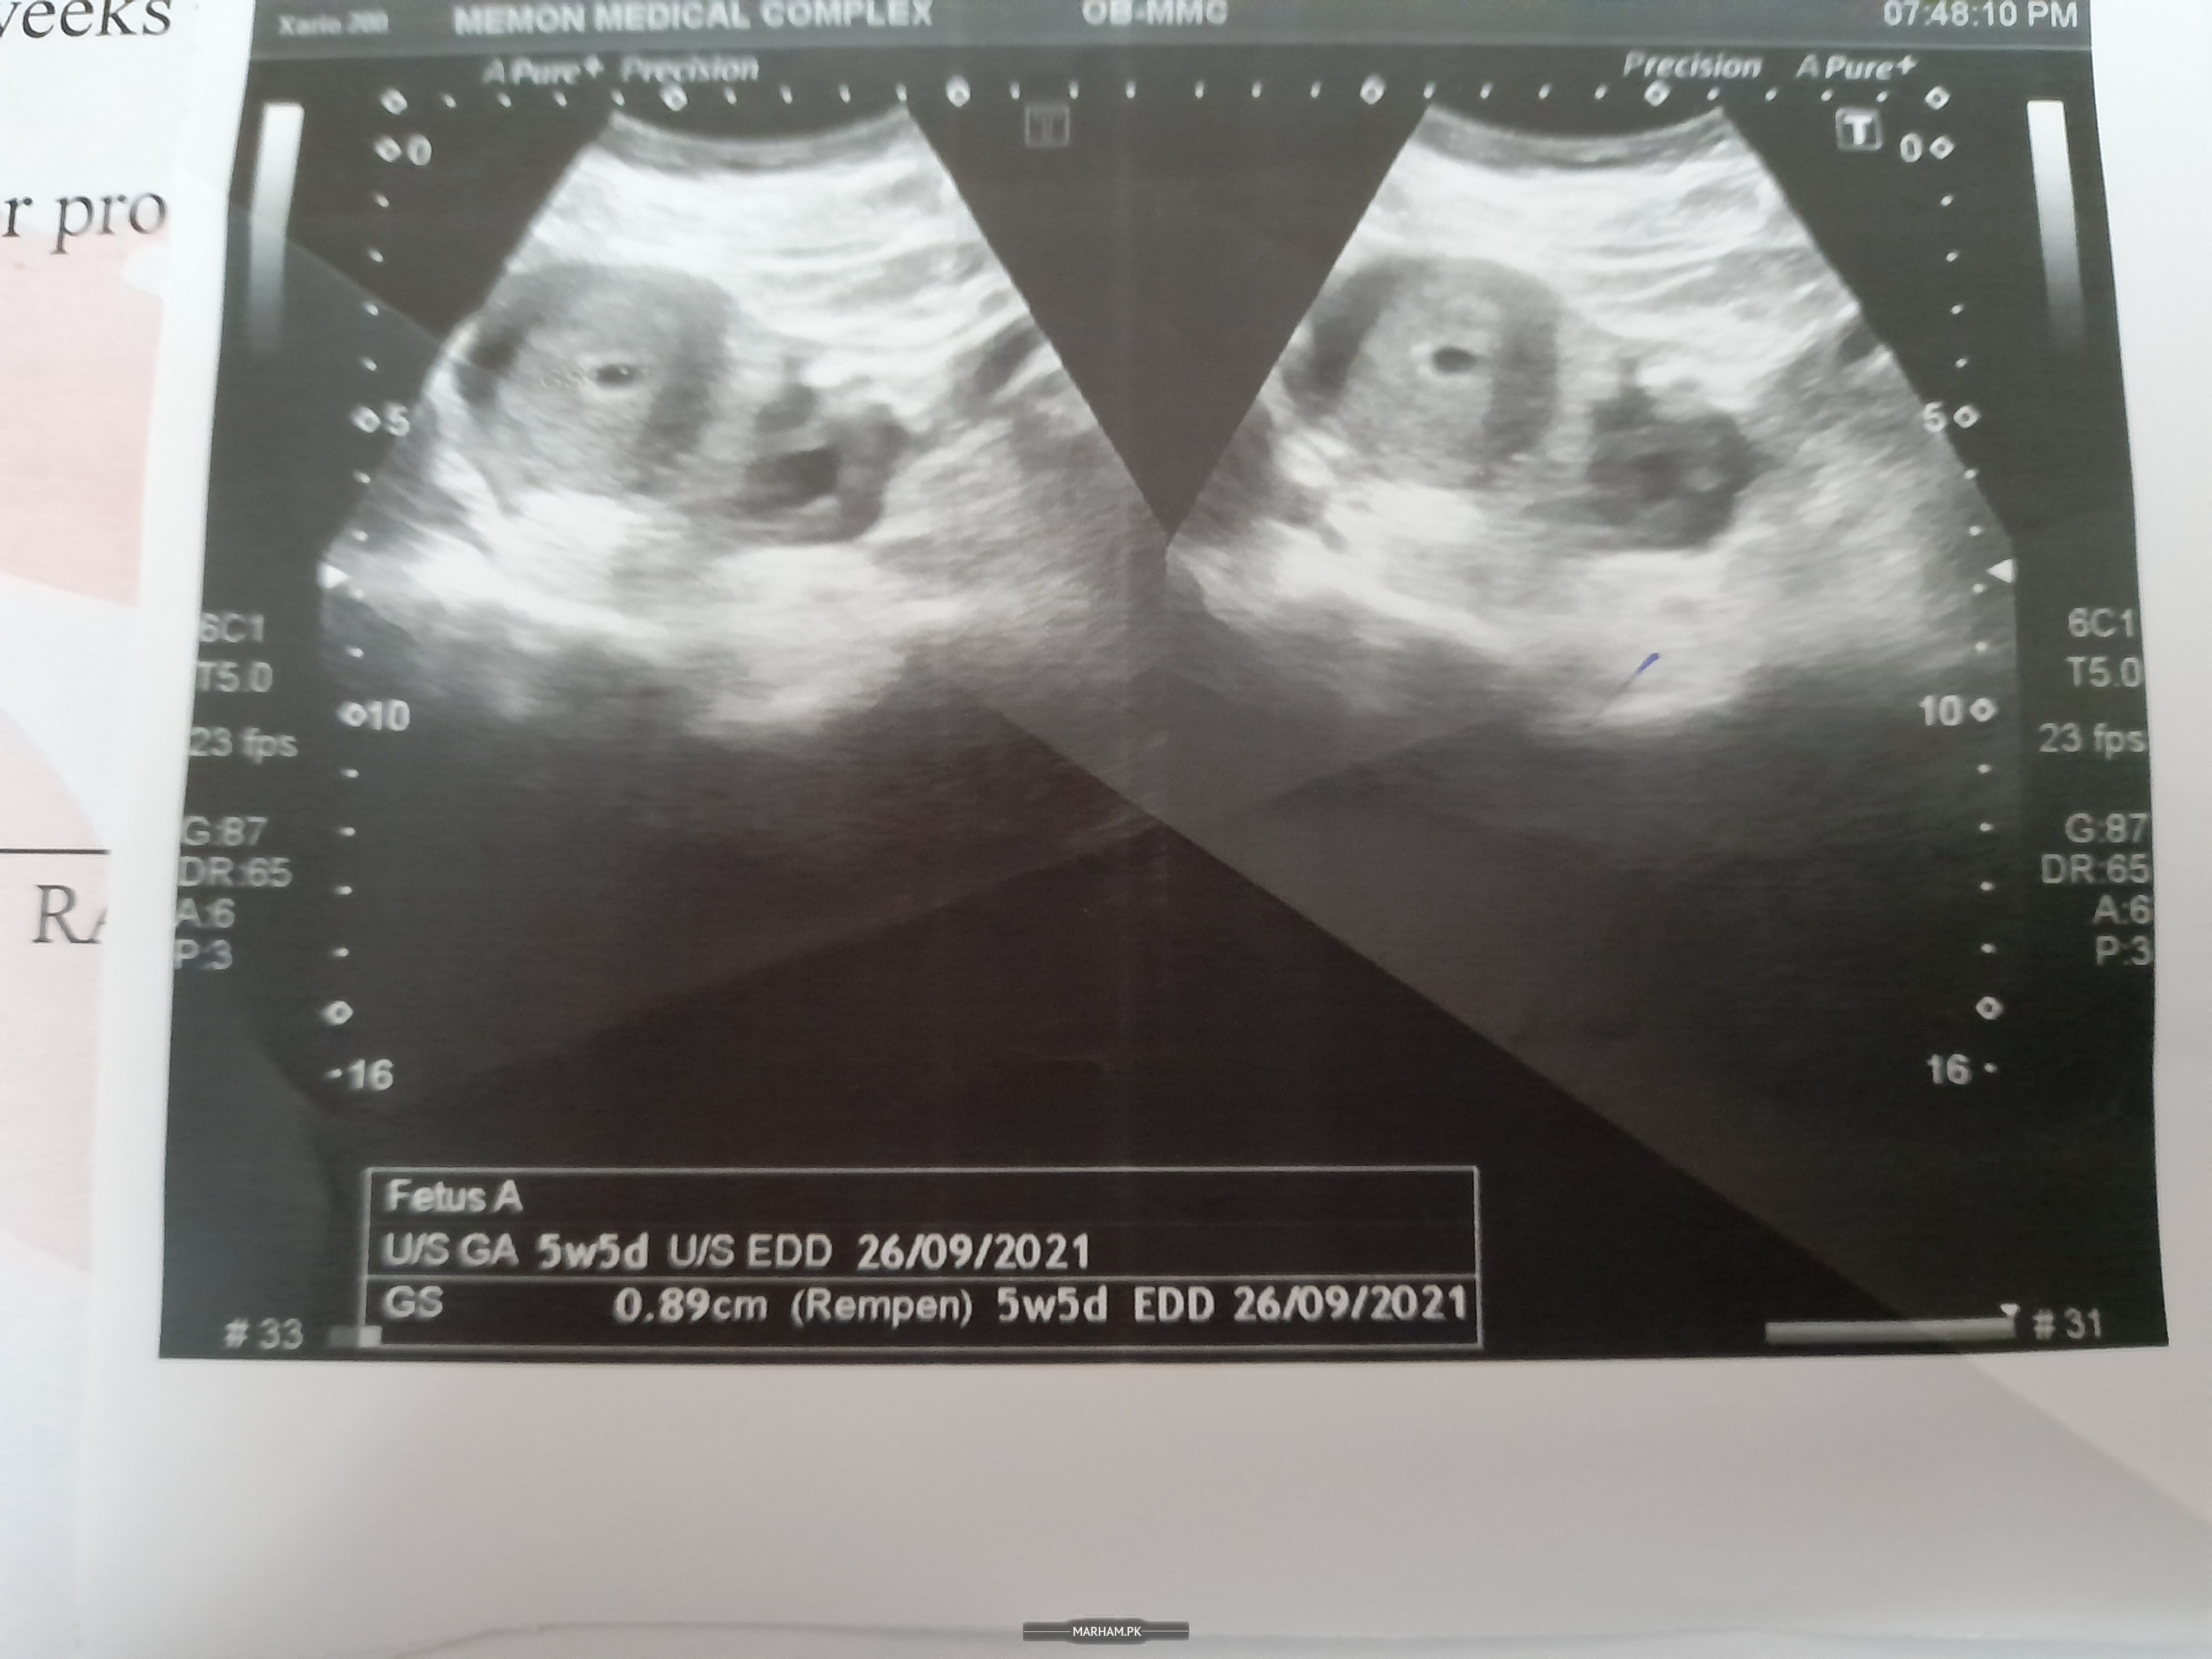

this is my scan

Walaikum assalam. Are u having any pain in abdomen. Please get an ultrasound scan as early as possible and share it's report with me. Meanwhile continue your medication . And why you taking ascard??

thank you sir, I am feeling slight pain in very lower part of abdomen. May be in carvix and very low pain in right leg